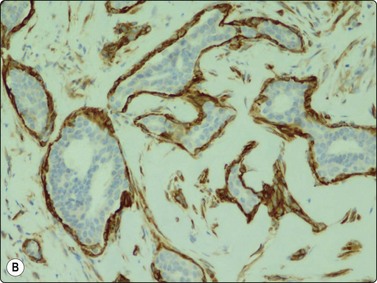

Phyllodes tumor (Figs 7.29-7.32)117-123

Phyllodes tumor (PT) is a biphasic epithelial/stromal neoplasm of the breast. In contrast to fibroadenoma, PT is a rare tumor comprising less than 0.3% of all breast tumors. It is classified as benign, low grade (borderline) and high grade (malignant) based on histologic features. Stromal cellularity and overgrowth, atypia, mitotic activity, and invasive growth pattern at tumor periphery define whether a PT is benign, low grade or high grade. Benign PTs do not metastasize, but may locally recur if incompletely excised. High-grade PTs behave like sarcomas with higher potential for recurrence and metastasis. Low-grade PTs fall in between.

image image

Fig. 7.29 Benign phyllodes tumor

(A) Huge, slowly growing breast mass in a 40-year-old woman; (B) FNB smears were cellular, dominated by dispersed cells with bare oval or plump spindle nuclei (MGG, HP).

Fig. 7.30 Borderline phyllodes tumor

Smears dominated by mildly atypical, both plump and slender spindle cells, single and in loose tissue fragments with fibrous stroma; a few sheets of bland duct epithelium (A, MGG; B, Pap, HP).

Fig. 7.31 Malignant phyllodes tumor

(A) Mainly dispersed spindle cells showing moderate nuclear atypia, no epithelial cells. Invasive growth demonstrated in tissue sections; multiple recurrences (MGG, IP); (B) Another case showing numerous spindle cells with more marked atypia and a sheet of bland epithelium (Pap, HP).

image

Fig. 7.32 Fibroadenoma mimicking benign phyllodes tumor on core needle biopsy (H&E, IP).

Aspiration biopsy can accurately diagnose malignant PTs in most cases. On the benign/borderline end of the spectrum, cytologic features of fibroadenoma and PT overlap, making FNA diagnosis difficult (see Fig. 7.23). Precise preoperative distinction is important for optimal patient management. Classic cytologic features in PT are similar to fibroadenoma. However, as opposed to fibroadenoma, stromal fragments are larger, increased in number (stromal overgrowth) and are hypercellular (phyllodes fragments); the single stromal cells in the background are plumper than the typical oval bare nuclei seen in fibroadenoma. These single cells are intact spindled cells with retained cytoplasm (not naked nuclei), and variable degrees of nuclear atypia with nucleoli and pleomorphism. However, some of these features may be entirely lacking in benign and low-grade PTs even after retrospective review of smears, making their differentiation from fibroadenoma virtually impossible. It is not surprising that a considerable portion of benign and low-grade PTs are initially diagnosed as fibroadenoma on cytology.117,120,121 This in part reflects sampling problems as hypo- and hypercellular areas tend to alternate within PTs. Another important diagnostic pitfall in PTs is the presence of significant epithelial proliferation including atypical ductal epithelial hyperplasia. If these areas are sampled by aspiration biopsy, this may lead to a false diagnosis of epithelial neoplasm. In our experience, we encountered this problem even with high-grade (malignant) PTs; one such retroareaolar case required core biopsy due to inability of aspiration biopsy to rule out an atypical papillary lesion. In addition, focal malignant transformation may be missed by FNA sampling.

Page 174

The diagnosis of PT on CNB is equally as challenging (Fig. 7.32). It is especially difficult to differentiate cellular fibroadenoma from benign/low-grade PT. In comparison, in one study, the possibility of PT was raised in 23% on FNB and 65% on core biopsy.122 In two others, 11 of 44 (25%), and 9 of 23 (39%) of surgically resected PTs were reported as fibroadenoma or benign on core biopsy.123,124 Similar to FNB, some PTs are diagnosed as fibroadenoma on core biopsy because of tumor heterogeneity. Marked nuclear pleomorphism and mitotic activity suggest frankly malignant phyllodes tumor (Fig. 7.31A,B).